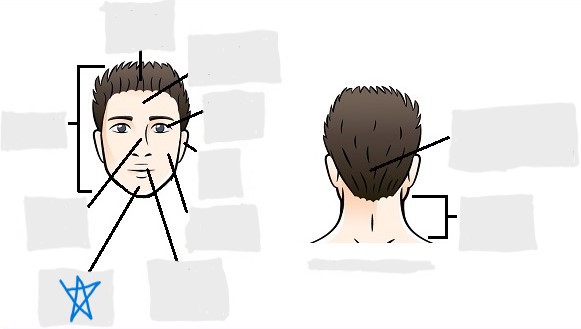

axial

cephalic

occipital

frontal

otic

orbital

nasal

oral

mental

cervical